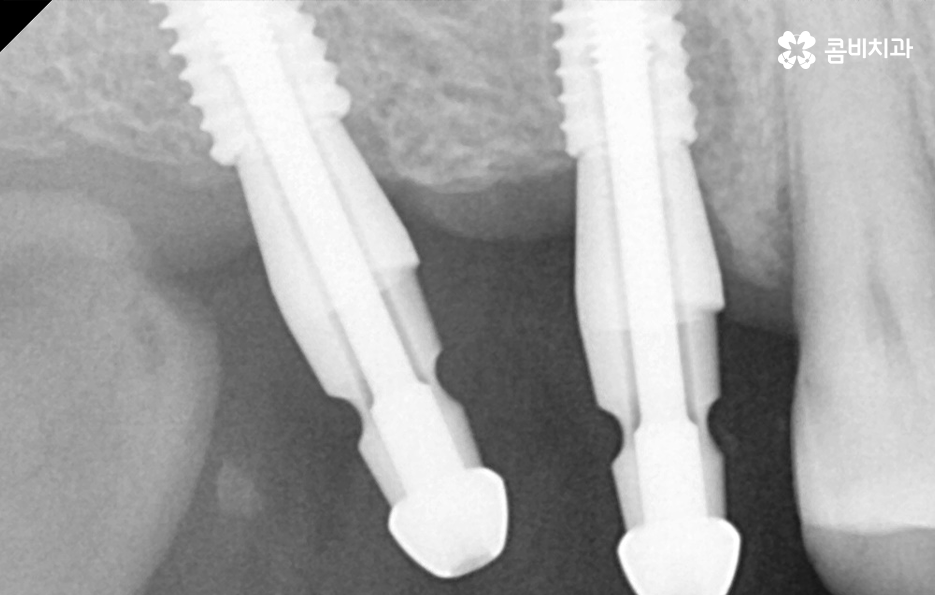

일반적인 임플란트의 치료 과정은 충치나 치주염 등으로 치아를 발치하게 되었을 때 치아 발치 후 잇몸이 아물고 회복되기를 기다리고 있는데요. 잇몸이 충분히 회복된 후에 임플란트를 잇몸 뼈에 식립하는 것을 시작으로 치과 내원과 어금니 임플란트 기간에 대해 대략적으로 알아보면 내원 횟수는 약 45회 정도로 예상되며 평균적으로 34개월 정도면 치료가 마무리 되고 있어요

여기서는 일반적인 치료 과정이라는 점을 전제로 하고 있는데요. 잇몸 뼈 상태가 양호하고 건강한 상태인 경우에 임플란트를 위한 치과 내원 횟수와 기간이 약 45회, 34개월 정도로 예상되는 것이며 잇몸 뼈의 상태가 좋지 않아서 뼈이식이 필요하거나 잇몸 이식술이 필요한 경우에는 치과 내원 횟수와 치료 기간이 더 늘어날 수 있는데요